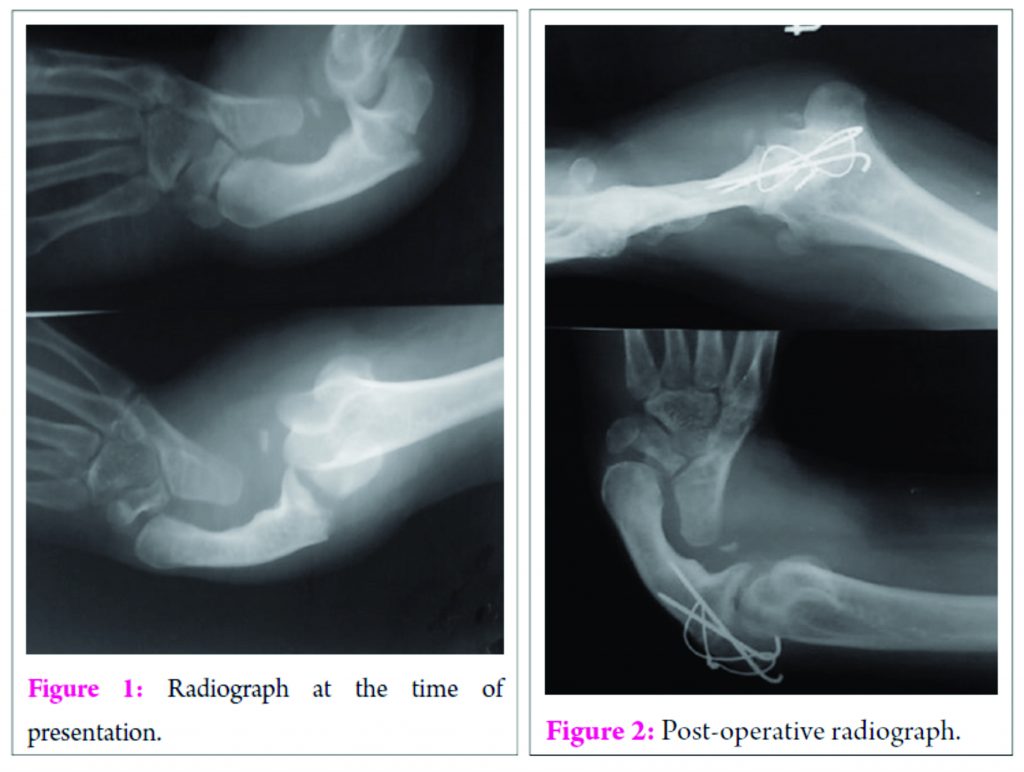

Case Report: We report the case of a 35-year-old male with radial club hand who presented with a transverse fracture of the olecranon process. The patient underwent open reduction and tension band wiring for the fracture. At 6 months follow-up, the fracture had united and the patient had a complete functional recovery.

A 35 year old male patient presented with pain of acute onset of the left elbow following a fall. Examination revealed a short and atrophied forearm with a single bone and tenderness over the olecranon process. All movements at elbow and forearm were restricted.A provisional diagnosis of RD was made with a traumatic event. Plain radiography confirmed the diagnosis of RD with a displaced transverse olecranon fracture. The limb was immobilised with an above elbow splint and following routine investigations and pre anesthetic checkup, was posted for surgery under regional block.

The olecranon was approached posteriorly. The fracture was exposed and reduced with small reduction forceps. Using a 2 mm drill, a hole was drilled about 5 mm away from the posterior cortex of ulna,2 cm distal to the fracture site. A 20 gauge cerclage wire was passed through the hole to leave segments on either side of the holes. Two 2 mm k- wires were passed from the olecranon directed towards the anterior cortex .The cerclage wire was passed beneath the triceps tendon and the k- wires and tightened in a figure of eight configuration. The protruding ends of the k wires were cut before sinking them into the bone. Hardware position and reduction were confirmed under an image intensifier and fracture stability and movements were checked.

Post operatively, the limb was splinted with the elbow in flexion for 1 week and physical therapy was started as tolerated by the patient. During the 6 month follow up range of movement at elbow was 20- 130 degrees, which was comparable to the normal side.

Tension band wiring was chosen as the treatment option after confirming with the patient about his functional range of movement before the fracture (20- 130 degrees), as the tension band wiring principle only exists during active extension in a range of 30-120° of flexion of the elbow8. Also, Post operatively, we were able to attain full range of motion which was comparable to the opposite side at6 month follow up. The tension band principle as applied to transverse olecranon fractures is based on the premise that distraction forces on the outer cortex of the ulna during elbow flexion are converted to compression forces on the articular surface of the olecranon at the fracture site. Hardware failure and secondary dislocations have been reported. Hardware failure was expected in this case due to the deformity and due to single bone articulating with the elbow, but we did not come across these complications. In our case tension band showed good results even when the bone in deformed and in the absence of the radius.